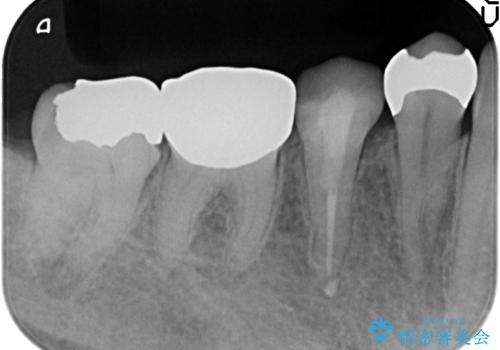

- 甘いものを食べると右下4番目の歯がしみるので診て欲しいといらっしゃった方の症例です。

古い銀歯と虫歯を除去後、PGA(ゴールド)インレーによる修復を行いました。